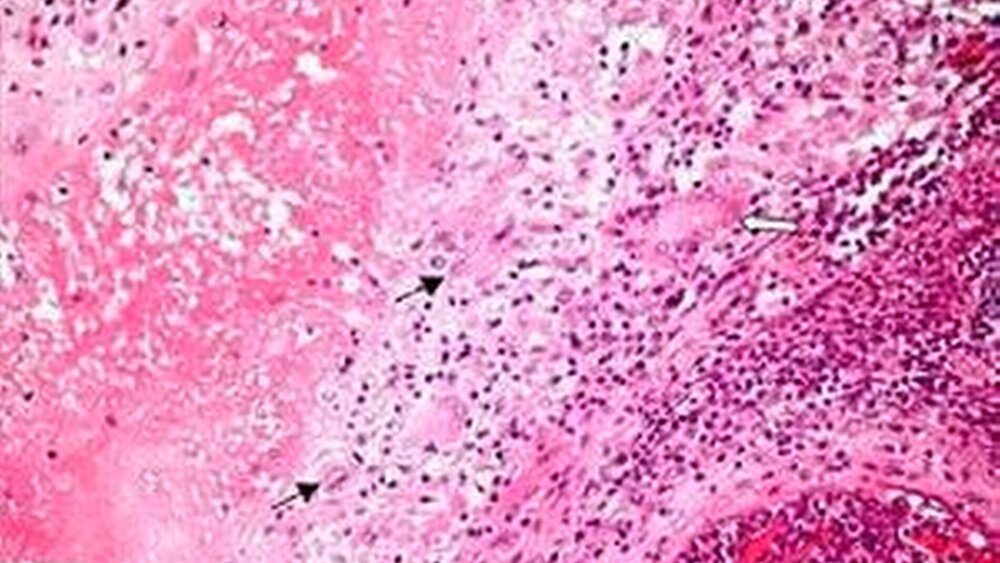

Die Indikation zur chirurgischen Revision ergab sich durch die Persistenz des Befundes unter der spezifischen antibiotischen Therapie. Es erfolgte eine spindelförmige Umschneidung der Infiltratzone sowie die Exstirpation des Fistelganges gemeinsam mit dem die Entzündung unterhaltenden Lymphknoten (Abb. 3). Im Anschnitt des Op-Präparates (Abb. 4) stellen sich sowohl im Lymphknoten als auch unmittelbar subkutan typische granulomatöse Herde dar. In der histopathologischen Aufarbeitung zeigten sich entsprechend ausgedehnte Granulome mit zentralen käsigen Nekrosen, umgeben von einem Lymphozytenwall mit Epitheloidzellen und histiozytären Riesenzellen vom Langhans-Typ (Abb.5).